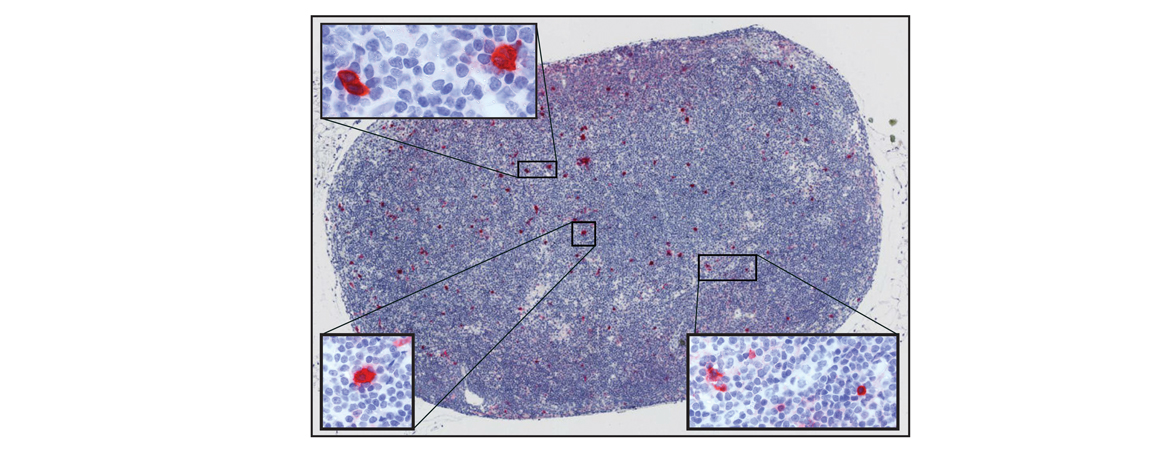

Veronika Lysenko, Donal McHugh, Lena Behrmann, Mary-Aude Rochat, Christian M. Wilk, Larisa Kovtonyuk, Jean-Pierre Bourquin, Christian Münz, Markus G. Manz, Roberto Speck, Alexandre P.A. Theocharides (Author)